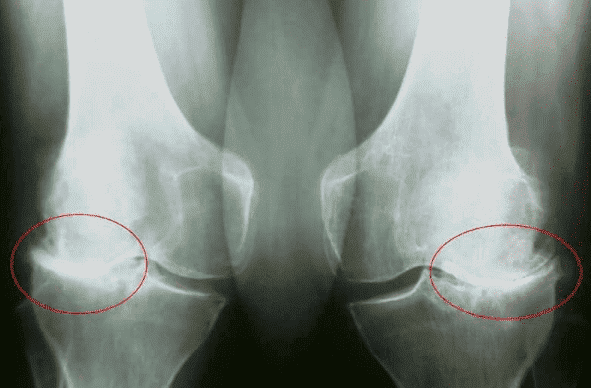

Gustavo Bueno: Padezco de problemas en las rodillas, con gonartrosis en estadio 3. Me diagnosticaron hace 5 años. La culpa es mía, porque lo dejé de lado. Debería haber empezado a tratarlo antes, pero lo único que hice fue tomar analgésicos - No podía interrumpir el rodaje, es nuestro trabajo. No importa el dolor, tengo que estar en el rodaje, de lo contrario defraudaré a todo el equipo.

Dra. Maria Isabel Mimbela Caballero: Las principales complicaciones de las patologías articulares son los cambios en la forma de las articulaciones, una fuerte limitación del movimiento y la anquilosis, que inmoviliza completamente la articulación y la fija en una posición, a menudo incorrecta..

Cuando las articulaciones no se flexionan y extienden completamente, se alteran los ejes de las extremidades, a lo largo de los cuales se distribuye la carga mecánica principal del cuerpo. Debido a la violación sistemática del eje correcto de la extremidad, aumenta la carga sobre otras articulaciones, lo que provoca cambios degenerativos secundarios.

Esto es especialmente importante cuando se trata de articulaciones que soportan peso: rodilla, cadera, tobillo.

Una persona experimenta DOLOR EXTREMO EXCRUCIANTE, la calidad de vida del paciente se reduce: la persona no puede moverse con normalidad, realizar las tareas domésticas cotidianas; se ve obligada a cambiar de trabajo, a renunciar a sus aficiones, y queda discapacitada en el 80% de los casos.